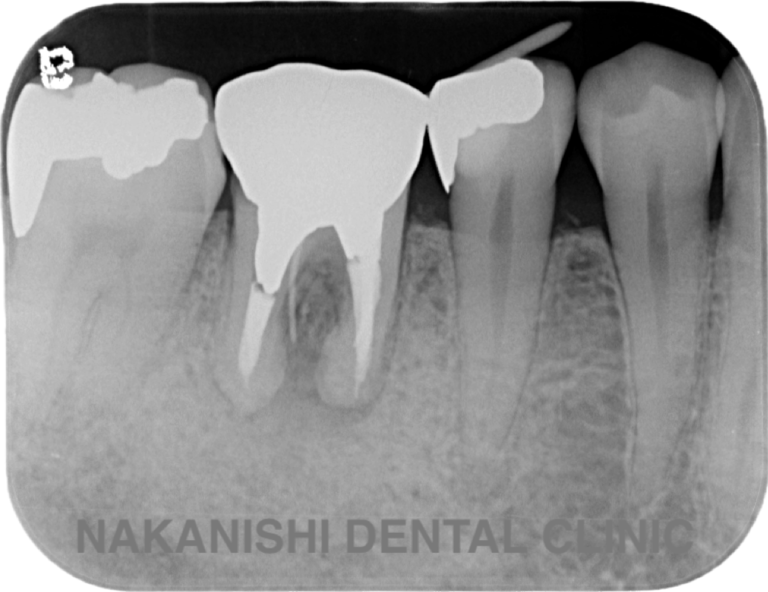

case 3.

治療前

治療後

| 主訴 | 左下奥歯が痛い、歯ぐきの腫れ。 前医で抜歯を提案されたがセカンドオピニオン希望でご来院。 |

|---|---|

| 治療期間 | 約半年(6か月) |

| 治療費 | 約5万円 |

| 治療内容 | 前医ではラバーダム不使用であったため、ラバーダム、マイクロスコープ下にて根管治療を施術。 痛みは消失したが腫れは治らなかったため、意図的再植を行い腫れは消失した。治療後のレントゲンは意図的再植後3年経過したもの。 |

| 治療のリスク | マイクロスコープやCTを使用し、可能な限り精密な根管治療を行っていますが、歯根の形態や病変の大きさ、過去の治療履歴などにより、治癒が得られない場合があります。 また、治療後に再感染や歯根破折が生じることもあり、その場合は再治療や抜歯が必要となることがあります。 治療結果には個人差があり、すべての症例で同様の経過を保証するものではありません。 |